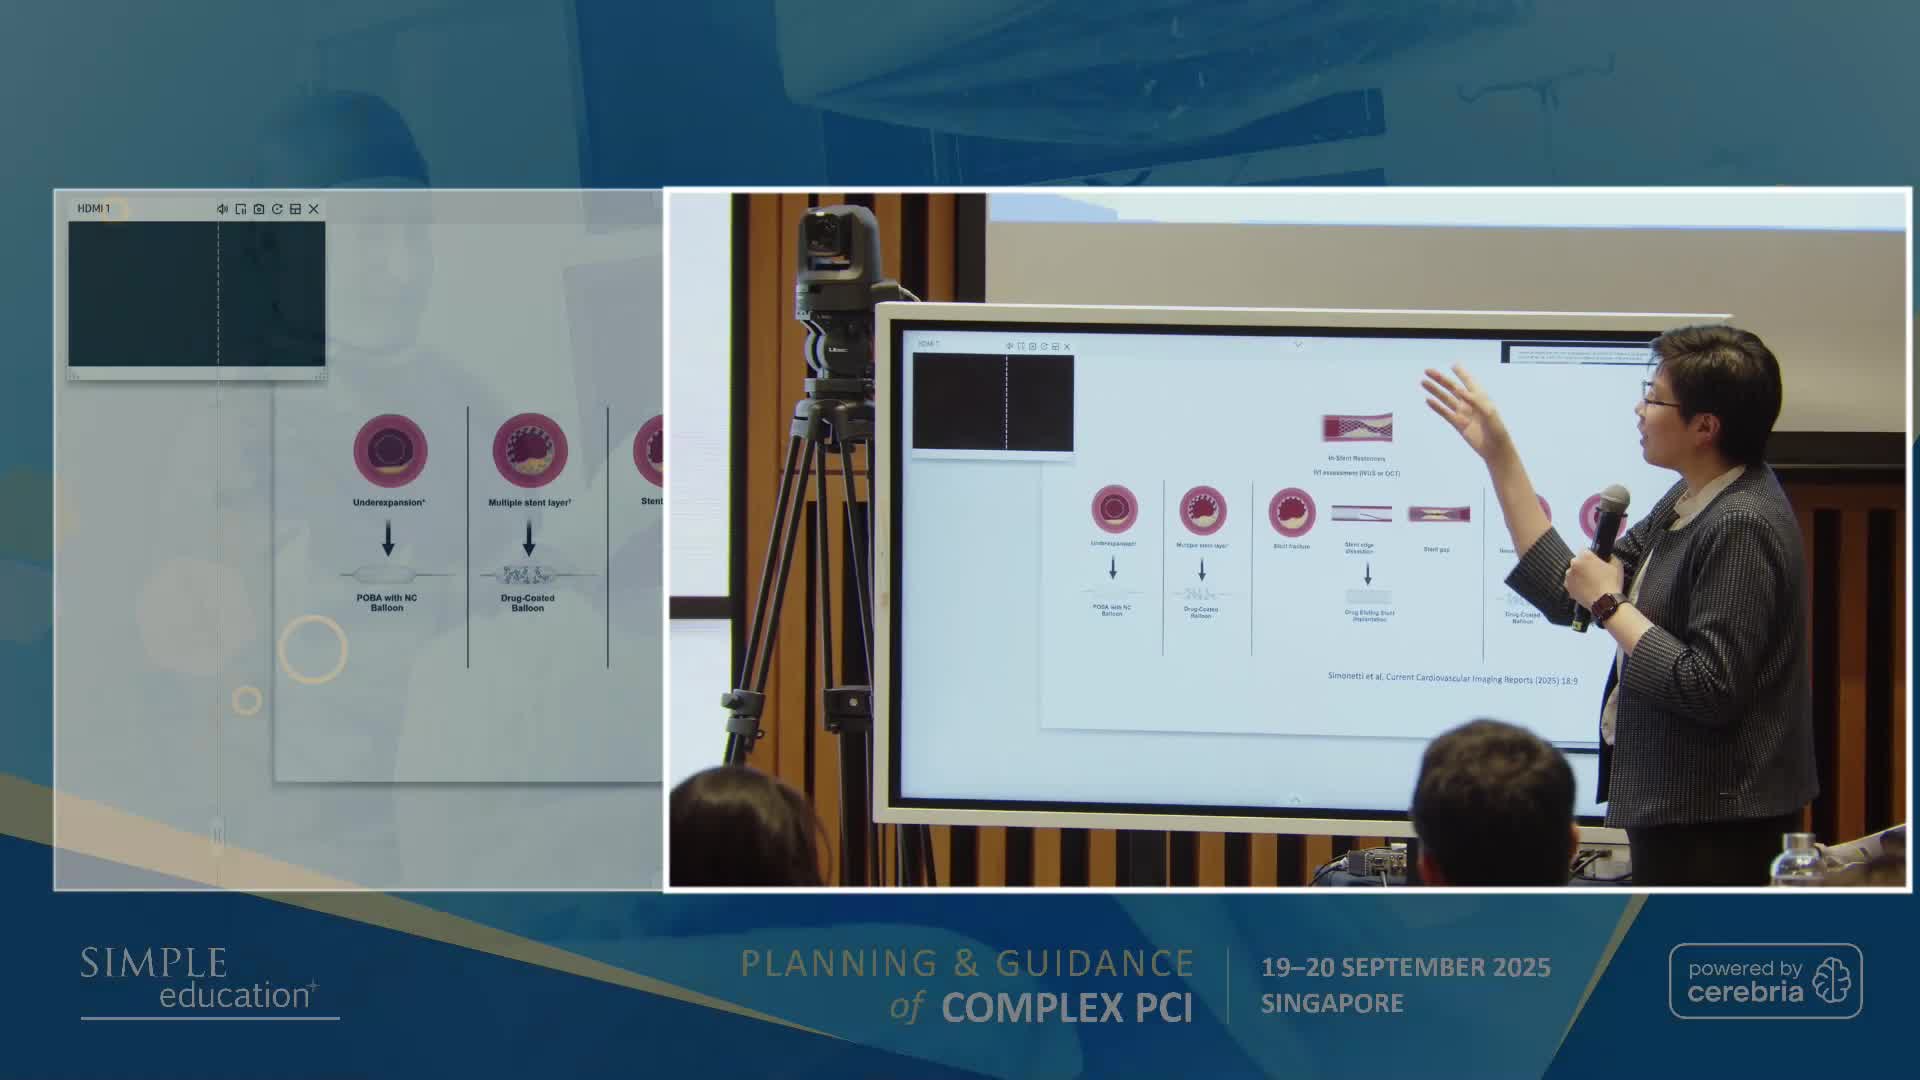

Ultralow Contrast PCI in complex and high risk patients - April 2024 Day One

Ultralow Contrast PCI in complex and high risk patients - April 2024 Day Two

Ultralow Contrast PCI in complex and high risk patients - November 2023 Day One

Ultralow Contrast PCI in complex and high risk patients - November 2023 Day Two

Ultralow Contrast PCI in complex and high risk patients - June 2023 Day One

Ultralow Contrast PCI in complex and high risk patients - June 2023 Day Two